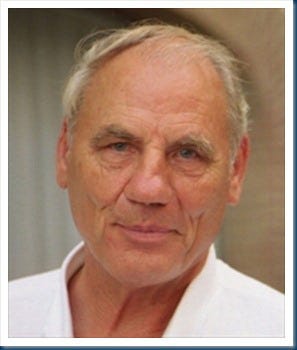

Doctor Ryke G. Hamer (1935 – 2017) developed testicular cancer after his grievous loss and began to wonder (if?) how the incidents were related. Hamer’s system, called New German Medicine (GNM), states the beginning of every disease (not caused by obvious bullet wounds, bad diet, poisonous substances etc.) is due to an unresolved mental conflict. Having a deathly ill child or losing a child would qualify as one such conflict of mind. Dr. Hamer’s work is believed to be “logically contradictory and scientifically implausible” by establishment medicine and since GNM’s inception in 1981, it has remained highly controversial and Hamer has been jailed for his ideas.

Wiki’s official Ryke Geerd Hamer page reads (edited): “[Hamer] was investigated, arrested and convicted several times in various European countries for crimes of medical malpractice, abusive practice of medicine, slander, fraud and has been disbarred, suspended, and is known for his anti-Semitic views and statements.”

Fascinating, weighty and suggestive as the details are, the fact is Hamer did develop a new grasp of the origins of disease based on his psychological grief in losing a child, though rather than being truly new it was also known in some form by the ancients.